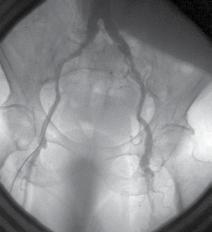

Multifocal arterial disease - surgical strategies

Ateroscleroza este o boală sistemică care afectează mai multe organe și sisteme. Leziunea care trebuie tratată mai întâi este cea care prezintă cele mai multe simptome sau leziunea cu cel mai puternic impact prognostic. Boala coronariană poate coexista cu stenoza arterei carotide, anevrismele de aortă abdominală și/sau boala arterială periferică (BAP).

Studii recente au confirmat faptul că pacienții cu boală multivasculară au un risc mai mare de evenimente cardiovasculare majore decât pacienții cu afectare monovasculară.

Leziunile vasculare trebuie tratate astfel: leziuni carotidiene, leziunile coronariene și leziunile aortice sau periferice. Când două teritorii arteriale sunt simptomatice (ex: AAA mai mare de 7 cm în diametru sau în iminența rupturii, asociat cu boala coronariană stângă) putem efectua proceduri simultane (deschise sau endovasculare), dar cu o rată a mortalității semnificativ mai mare.

Atherosclerosis is a global disease affecting multiple organs. The symptomatic lesion or the lesion with the strongest prognostic impact should be treated first.

Coronary artery disease may coexist with carotid artery stenosis, abdominal aortic aneurysms, and/or peripheral artery disease (PAD).

Recent studies have confirmed that patients with multivascular bed disease have a greater risk for major cardiovascular events than patients with monovascular attempt.

The lesions should be treated as follows: carotid, coronaries and aorta or peripheral lesions. When two arterial beds are symptomatic (ex: AAA more than 7cm in diam. or in imminence of rupture associated with left main disease) we can perform simultaneous procedures

(open or endovascular), but with higher mortality rate (25%).

• Vascular patients often have concomitant arterial disease affecting more than one territory.

• Identification of silent vascular disease is essential to improve cardiovascular mortality and morbidity rates.

• The treatment of multifocal arterial disease should include aggressive risk factor management, lifestyle changes, and appropriate drug therapy.

Fig. 2 – Predicting multi-vascular diseases in patients with coronary artery disease [3]

In these polivascular patients, cardiac complications are:

• in aortic surgery = 4% - 8%

• in carotid surgery = 2%

Fig. 1 – Prevalence and probability of panvascular disease according to age [1]

In patients with multifocal arterial disease, myocardial revascularization is indicated before the vascular intervention, with the exception of carotid lesions.

To avoid the unnecessary coronarographies, it is mandatory to identify the predictive clinical parametres for myocardical revascularization (surgical or interventional).

The surgical treatment of panvascular disease puts today difficult therapeutic strategies and often controversial.

Today’s treatment:

CABG before aorto-iliac revascularization with a waiting interval of 1-2 months.

For a simultaneous surgery (CABG + terminal Aorta surgery), a rigorous selection of the patients must be made:

• young age

• good general status

• no obesity

• no COPD

In our clinic, in 2003 on one year period, on 400 direct arterial revascularisa-

tions we had 11 patients with multiple sites of atherosclerotic disease. The decade more affected was 60 – 70 years old. After 20 years, in 2023, the number of patients increases a lot, at 120, and the patients were older. (decade 70-80 y). Man were more affected.

Conclusions:

• The treatment must be personalized, decided by a multidisciplinary team

• Priority: the most symptomatic lesion or the one with the strongest impact

• It is unanimously accepted the therapeutic strategy:

• carotid – coronary – peripheral

• Panvascular disease = complex management.

In PVD patients, the prevalence of the coronary insufficiency is at least 40%50%, while myocardial revascularization is between 10% and 25%.

The prevalence of the carotid artery stenosis is 10,5%.

Coronary lesions and/or carotid ar-

tery lesions, even when treated, represent a significant risk factor of post-surgical death. It needs a systematic pre-operative screening.

Fig. 5: Coronary Three-Vessel Disease: LAD, Cx, RCA

Fig. 7: right common iliac stenosis, occlusion of superficial femoral artery bilateral

Fig. 8: LIMA on LAD and two vein grafts on Cx and RCA

Fig. 6: Carotid TEA